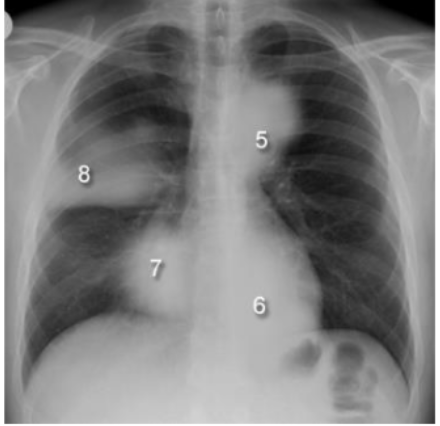

What are these silhouette signs? what causes them?

5: aortic knuckle (anterior mediastinal or L upper lobe disease), 6: paraspinal line (post thorax disease), 7: R heart boarder (middle lobe disease) 8: density above horizontal fissure